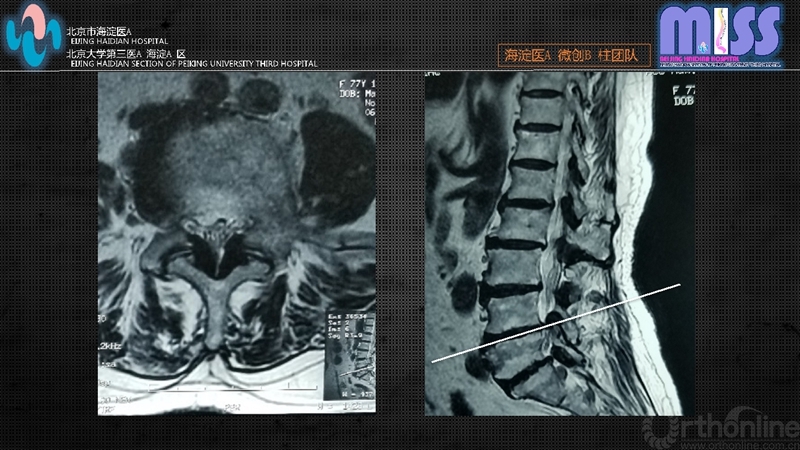

(2)CT和MRI检查证实为腰椎管狭窄,致压物主要为后方肥厚的黄韧带及增生内聚的关节突关节

依据上述标准,2016年1月至2017年6月共34例患者入选,全部采用经皮全内窥镜下经椎板间隙单侧入路双侧减压术,其中男19例,女15例;年龄65~88岁,平均71.9岁;病程0.5~8年,平均2.3年;单侧下肢症状为主8例,双侧下肢症状26例。其中L4/5节段22例,L5/S1节段12例。